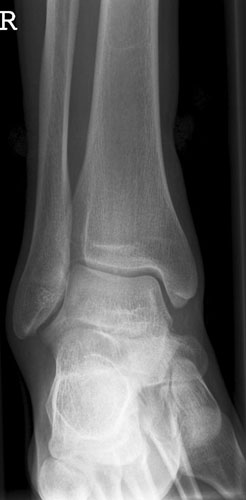

OSG a.p.

Fehler

Außenrotation bzw ungenügende Rotation des Fußes nach innen. Der mediale Gelenkspalt projiziert sich besonders schön frei, hingegegen ist der laterale Spalt verschattet.

Abhilfe

Fuß weiter nach innen drehen lassen, bis beide Malleolen auf einer Höhe parallel zum Film stehen.